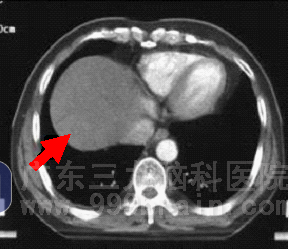

来自江西的殷某,3月前发现腹部包块,质地硬,无压痛,进食后有稍许腹胀感,未出现厌食油腻及全身乏力等不适,至当地医院检查诊断为肝癌,行介入治疗。治疗后一月复查示肿瘤较前增大。患者经多方了解后转至广东三九脑科医院求治,肿瘤综合治疗中心李明众教授予病人查体时发现患者肝右叶包块,巩膜轻度黄染,查肿瘤标志物甲胎蛋白值远远高于正常,患者除有进食后腹胀感外,其他一般情况良好。肿瘤综合治疗中心专家组审慎讨论了病例,经研究讨论决定给患者行适形放疗,放疗期间同步予化疗。放疗完成55Gy后复查CT片示巨块型肿瘤已消失,肿瘤标志物甲胎蛋白值恢复正常,患者自诉上腹饱胀感明显好转。

▲治疗后